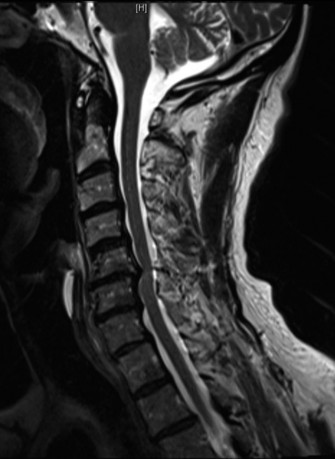

CASE 1 A 63-year-old male sustained a hyperextension injury to his neck while diving into a pool. Upon presentation, he reports decreased sensation in his hands and decreased strength in his arms and wrists, but no lower extremity complaints. On motor examination, he has 5/5 strength in his deltoids and elbow flexors and 4/5 strength in the elbow extensors, wrist extensors, and finger flexors. Lower extremity motor examination is normal. Sensation is decreased to light touch in both hands. Otherwise his sensation is preserved. Images of his cervical spine are shown in Figures 1–1 to 1–3.

Figure 1–2

The correct answer is (B). The clinical scenario describes a patient with central cord syndrome (CCS). CCS continues to be the most common incomplete spinal cord injury accounting for 15.7% to 25% of all spinal cord injuries. The characteristic presentation is an extension moment injury in a previously spondylotic and stenotic spine. Figures 1–1 to 1–3 demonstrate a spondylotic spine with central narrowing and CSF effacement that is worst at the C3–4 level. Bleeding, edema, and/or Wallerian degeneration lead to damage of the lateral corticospinal tract which is the main descending motor tract in the spinal cord. The more central anatomic position of the homunculus to the upper extremities places them at greater risk than those to the lower extremities. As such, injury to the lateral corticospinal tract is characterized by upper more than lower extremity involvement and motor deficits being more pronounced than sensory deficits.